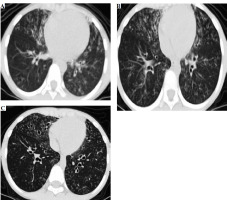

After admission, based on the pulmonary CT scan and pathogen metagenomics of BALF, the child received anti- infection treatment with cefoperazone-sulbactam. Notably, the child had been hospitalized in 2018 for drowning, and a pulmonary CT scan from September 3, 2018 (Fig. 1A) revealed extensive bronchiectasis with infection, but he did not undergo further follow-up after discharge. The current admission’s pulmonary CT showed bronchiectasis with infection and extensive small nodular shadows (Fig. 1B), considering the child’s history of recurrent respiratory infections, sinusitis, otitis media, and warts, suggesting a possible immune deficiency, leading to a recommendation for genetic testing.

Fig. 1

The chest CT of the patient showing bronchial dilatation with infection and diffuse nodular changes in both lungs

After 7 days of anti-infection treatment, follow-up bronchoscopy showed improved bronchial mucosal inflammation, no purulent secretion, significantly reduced cough and expectoration symptoms, and disappearance of lung signs. A high-resolution pulmonary CT scan on March 22, before discharge, showed significant improvement in bronchiectasis and lung infiltrates compared to previous findings (Fig. 1C).